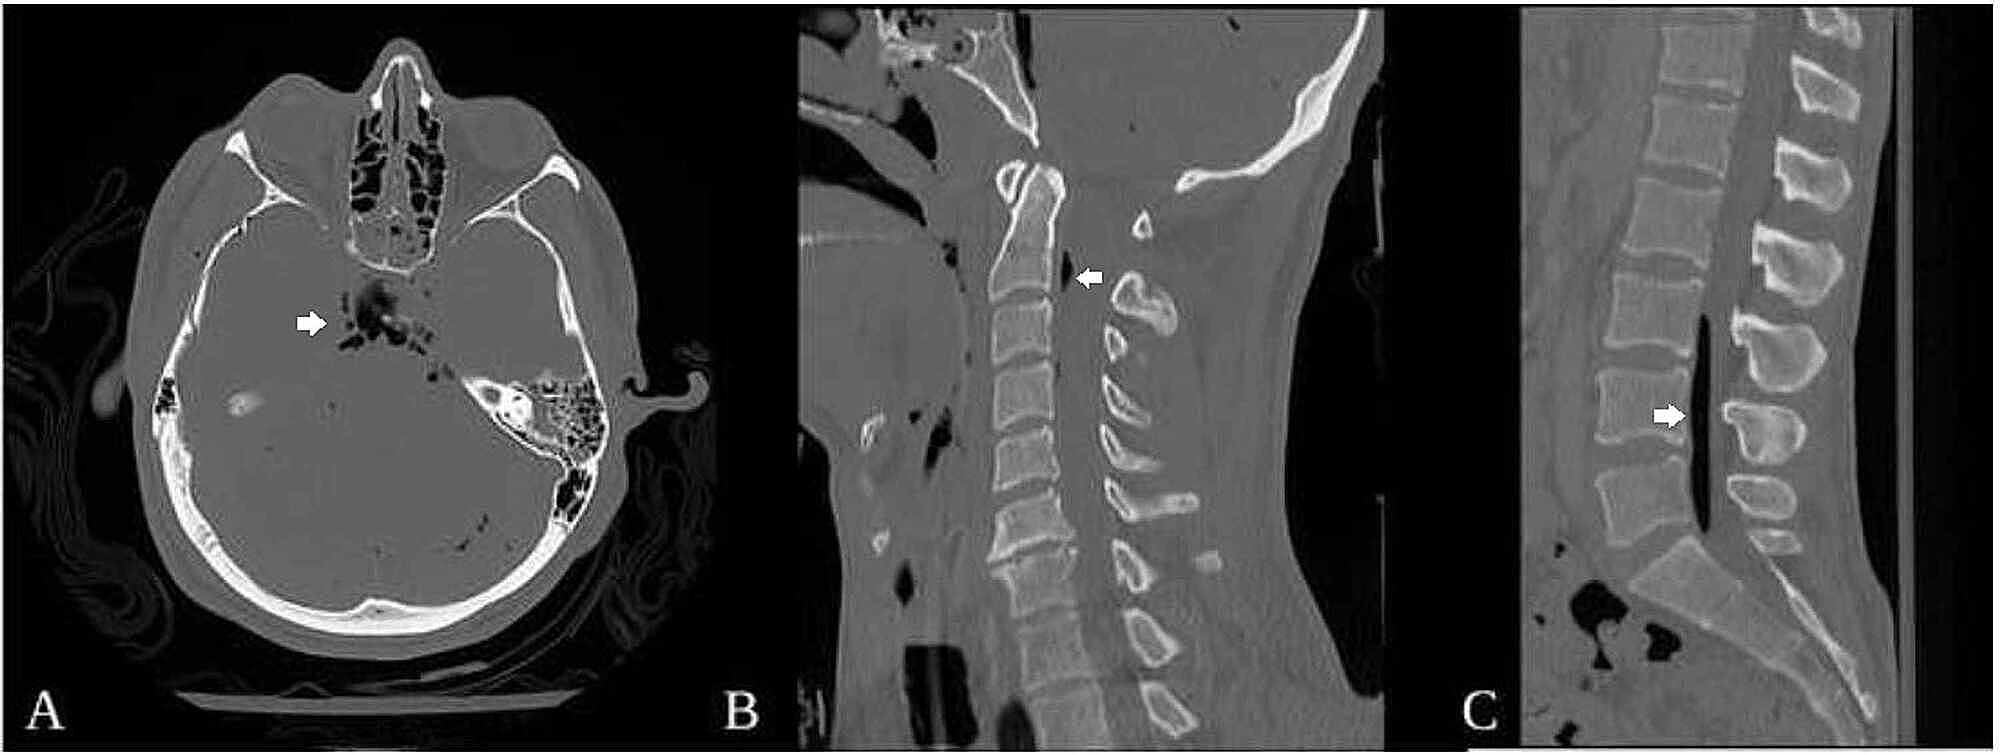

CT of the head without contrast revealing (a) pneumocephalus and (b Basilar Skull Fracture Pneumocephalus basilar skull fracture, pneumocephalus. when pneumocephalus is suspected, ct can play a vital role in determining the precise location of the gas collection, its. — basilar skull fractures are commonly encountered in the trauma setting. — the main cause of pneumocephalus in 75% of patients is neurotrauma, especially with the presence. — a basilar skull. Basilar Skull Fracture Pneumocephalus.

Cureus Lumbar Pneumorrhachis Associated With Basilar Skull Fractures Basilar Skull Fracture Pneumocephalus — basilar skull fractures are commonly encountered in the trauma setting. — the main cause of pneumocephalus in 75% of patients is neurotrauma, especially with the presence. basilar skull fracture, pneumocephalus. when pneumocephalus is suspected, ct can play a vital role in determining the precise location of the gas collection, its. — a basilar skull. Basilar Skull Fracture Pneumocephalus.

Cureus Lumbar Pneumorrhachis Associated With Basilar Skull Fractures Basilar Skull Fracture Pneumocephalus — the main cause of pneumocephalus in 75% of patients is neurotrauma, especially with the presence. when pneumocephalus is suspected, ct can play a vital role in determining the precise location of the gas collection, its. basilar skull fracture, pneumocephalus. — a basilar skull fracture is a variant of skull fracture occurring at the base of. Basilar Skull Fracture Pneumocephalus.